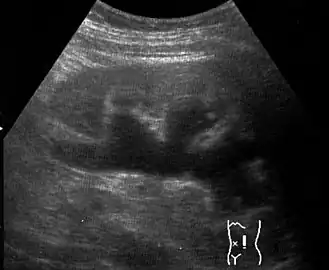

Гидронефроз (син. водянка почки[3]) — расширение почечной лоханки и чашечки на почве нарушения оттока мочи в пиелоуретеральном сегменте, которое может приводить к постепенной атрофии почечной паренхимы. Случаи заболевания в зависимости от возраста встречается у 0,6—4,5 % населения[4]. Основным признаком является расширение почечной лоханки — места, где скапливается моча после её производства[5]. В результате гидронефроза накопление мочи в одной или обеих почках может приводить к опуханию почек и увеличению их размера[6]. Гидронефроз обычно не вызывает каких-либо долгосрочных проблем, если был своевременно диагностирован, и вовремя было начато лечение[7].

Наряду с пиелоэктазией почек врождённый гидронефроз часто обнаруживается при ультразвуковом обследовании плода[4] во время пренатальных скринингов. Во время беременности обычно обнаруживается гидронефроз лёгкой степени, в подобных случаях считается, что он обычно вызывается повышенной выработкой мочи у плода. В большинстве случаев у грудных детей лечение может и не потребоваться[7].

Диагноз ставится на основании УЗИ, экскреторной урографии и ренографии.

При пренатальном диагностировании степень заболевания определяется размером почечной лоханки, замеряемым посредством УЗИ.